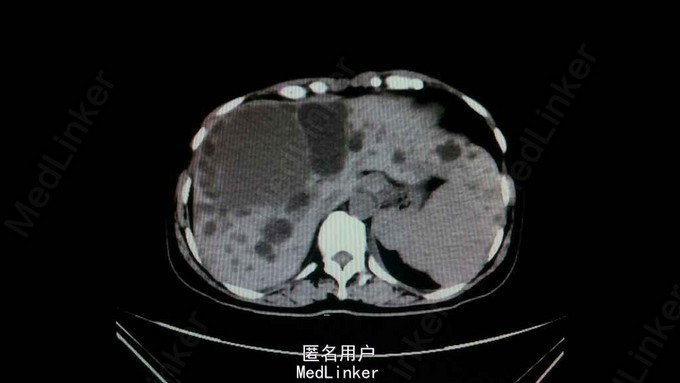

主诉:黑便2月 病史:患者2月前无明显诱因下出现黑便,量正常,成型;1周后伴有头晕、乏力。无恶心呕吐,无腹痛腹泻,无呕血等。至当地医院就诊,查血色素58g/L,腹部CT提示多囊肝,胃镜提示胃间质瘤。予输红细胞、血浆,护肝、营养等对症处理后头晕乏力症状好转。但一直以来持续有黑便。现为进一步治疗来我院就诊。

查体:未见明显异常 辅助检查:腹部CT提示多囊肝,多囊肾。胶囊内镜提示未见明显病灶、出血灶。

诊断:肝囊肿,消化道出血 处理:入院后完善相关检查检验,CT上发现大囊肿旁有一密度稍高类圆形影,不能排除是积血。行胶囊内镜未见胃肠道有明显出血灶。予输血、护肝、止血等对症治疗。推测有可能是囊肿出血经胆道引起消化道出血。行MRCP明确。